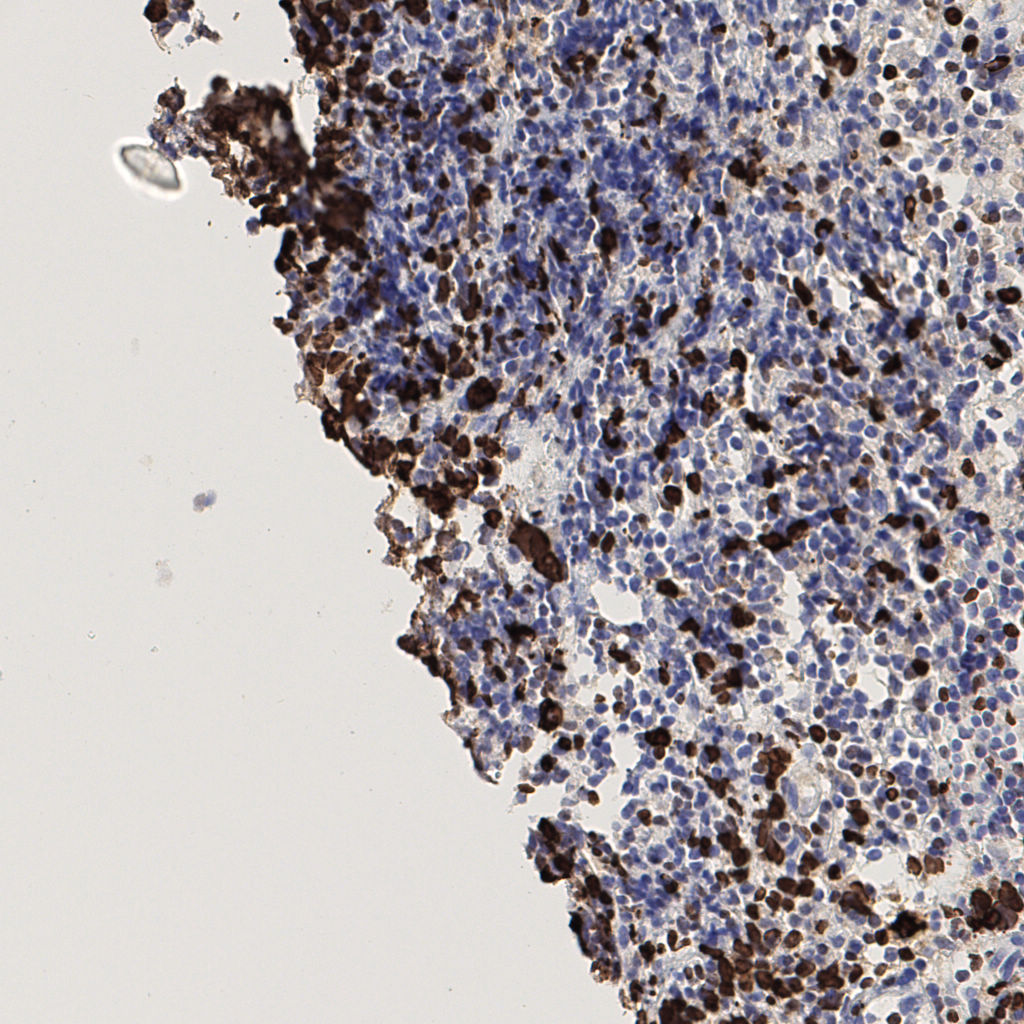

slice_42_5_x37632_y4480.png

slice_42_5_x37632...